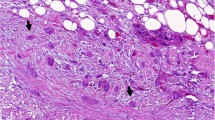

We used the following antigens as markers for detecting each of the cell types: CD68 for pan-macrophages, CD163 or CD204 for M2, CD66b for Neu, CD4, CD8, and FOXP3+CD4+ (Treg) for subsets of T cells. M1 were detected as HLA-DR+CD68+ cells (Figure 1). In 78% of the cases, M2 were predominant among tumour-infiltrating macrophages. In contrast, M1 infiltrated chronic pancreatitis (non-cancerous pancreas) predominantly. The majority of the macrophages that had infiltrated into areas of necrosis were M2. The density of tumour-infiltrating macrophages, CD4+T, and CD8+T was higher near the invasive front of the tumour, and that of T cells was lower at the centre of the tumour. Preliminary tests revealed that rather than the absolute numbers of infiltrating cells, it would be better if we used the ratio of FOXP3+CD4+ T cells to CD4+T (%Treg) and the ratio of M1 to pan-macrophages (%M1) as variables, as they were more representative of the biological characteristics of the respective infiltrating cells. Comparison of immune/inflammatory cells infiltrating into normal pancreas, chronic pancreatitis (non-cancerous pancreas), and PDC is shown in Figure 1I.

Immunohistochemical features of tumour-infiltrating immune/inflammatory cells. The representative photos are shown: (A) CD8+ T cells, (B) CD4+ T cells, (C) FOXP3+ T cells, (D) CD68+ pan-macrophages, (E) CD163+ M2 macrophages, (F) CD204+ M2 macrophages, (G) CD66b+ neutrophils, and (H) CD68+HLA-DR+ M1 macrophages (CD68 in brown and HLA-DR in purple). Scale bars show 10 μm in length. A comparison of infiltrating immune/inflammatory cells into normal pancreas, chronic pancreatitis (non-cancerous pancreas, and PDC is shown in I. Columns and bars show mean (n=20) and standard error, respectively. Significance values were *P<0.05 and **P<0.01.